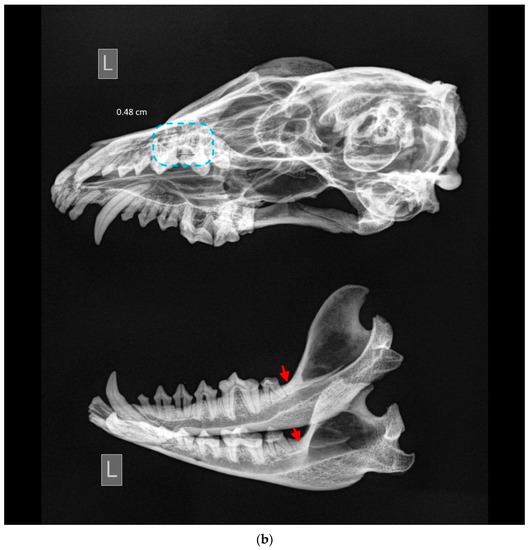

Other findings. One particular skull (ID M–3392; Figure 7a,b) is severely affected and includes a lot of various kinds of dental and non-dental pathologies. This case warrants a detailed description of its specific findings. An absence of third lower molar teeth was detected. Complicated horizontal dental fracture with necrotic pulp and severe periapical alveolar resorption is present in P4 and rostral root of M1 of the left side of the maxilla. Furthermore, third-stage periodontitis with mild alveolar resorption affects all premolar and molar teeth, and attrition affects the left side’s lower and upper canine teeth. A similar pattern of periodontitis is evident on the left mandible. Moreover, multiple osteophytes had developed in the region of the zygomatic bone and external sagittal crest and nuchal crest.

Figure 7.

ID M–3392, male. (a) Approx. length—120 mm. Third-stage periodontitis with complicated horizontal dental fracture and periapical bone resorption (marked by a blue square) in the raccoon dog’s left side of the maxilla. Blue arrow shows the attrition of the left upper canine tooth, and red arrow shows the mild alveolar resorption. (b) X-ray of third-stage periodontitis with complicated horizontal dental fracture and periapical bone resorption (marked by a blue square) in the raccoon dog’s left side of the maxilla. Red arrows show the absence of the lower third molar tooth. No tooth buds were found.